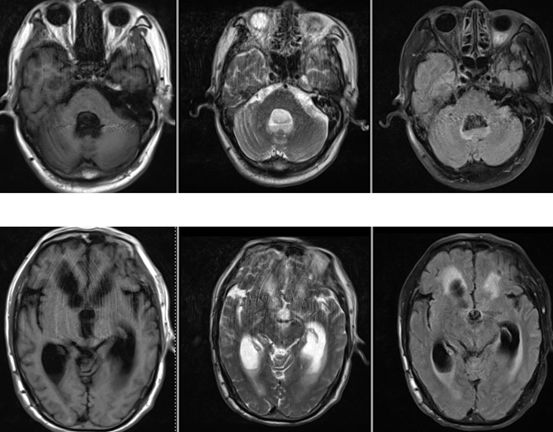

病例6

19岁,女性,头晕1年余。既往口吃,智力稍低下。查体:无明显阳性体征。

答案:Dandy-Walker畸形(变异型)

Dandy-Walker畸形典型三联征:小脑蚓部发育不良+四脑室囊样扩张+后颅窝扩大。

Dandy-Walker畸形可合并其他异常,70-90%可合并脑积水。

三联征不全,只有前两联,没有后颅窝扩大时,称为Dandy-Walker变异型。

该病例后颅窝扩张并不明显, 应该符合Dandy-Walker变异型。虽然到了周五,大家热情不减。有理有据的分析,不管是对是错,总是会有收获。